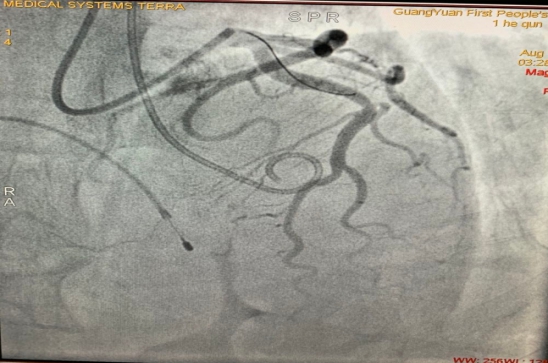

近日,市第一人民医院心血管内科一病区成功为一例厚梗阻型心肌病患者实施经皮穿刺室间隔心肌化学消融术。该手术不开胸、不借助体外循环,手术创口仅几毫米。术后,患者即感胸痛、呼吸困难明显缓解,第二天便可下床活动。

该手术的成功开展开创了广元地区此种微创方法治疗肥厚梗阻型心肌病的先河,标志着医院在结构性心脏病的介入治疗领域上迈出了坚实的一步。

何女士入院后,心血管内科一病区主任邓小军、副主任陈玺全与超声诊断科副主任邓仕军一同认真分析了该患者的病史和临床表现,结合患者超声心动结果考虑诊断:肥厚梗阻型心肌病患者有明确的室间隔基底段肥厚伴流出道梗阻,跨瓣压差大于50mmHg

明确诊断后,科室专家立即研讨治疗方案。为达到最佳治疗效果,邓小军主任,陈玺全副主任介入团队召集全科同仁术前仔细讨论病例,详细查阅文献,学习相关手术视频,借鉴国内领先介入手段,结合患者的临床特点,在征得患者及家属同意后,决定为该患者实施经皮穿刺室间隔心肌化学消融术。

2020810日,陈玺全副主任带领段青松主治医师在患者局麻,清醒的状态下,顺利完成了手术。手术过程经历近四个小时。术后,患者胸闷、胸痛症状明显好转,未再有晕厥症状出现。复查心脏彩超显示患者左室流出道梗阻症状及二尖瓣反流明显缓解,左心房大小降至正常水平,进一步证实了该手术在肥厚梗阻型心肌病治疗上的有效性。

经皮穿刺室间隔心肌化学消融术其原理是经过微创介入的方法经导管注射无水酒精,栓塞冠状动脉的间隔支,使其支配的肥厚室间隔心肌缺血、坏死,变薄,收缩能力下降,使心室流出道梗阻消失或下降,从而改善肥厚梗阻性心肌病病人的临床症状。